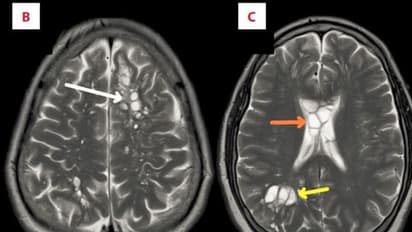

ಮೆದುಳಿನ ಎರಡು ಬದಿಗಳಲ್ಲೂ ಲಾಡಿ ಹುಳುಗಳ ಲಾರ್ವಾ ಕಂಡು ಬಂದಿದ್ದು, ಪರೀಕ್ಷಿಸಿದ ವೈದ್ಯರೇ ಶಾಕ್ಗೆ ಒಳಗಾಗಿದ್ದಾರೆ. ಇವು ಹಂದಿಗಳ ದೇಹದಲ್ಲಿರುವಂತಹ ಲಾಡಿಹುಳುಗಳ ಲಾರ್ವವಾಗಿದ್ದವು. ಈ ಅನಾರೋಗ್ಯಕ್ಕೆ ತುತ್ತಾದ ವ್ಯಕ್ತಿ ತಮ್ಮ ಜೀವನದುದ್ದಕ್ಕೂ ಹೆಚ್ಚಾಗಿ ಬೇಕನ್ ಅಂದರೆ ಸರಿಯಾಗಿ ಬೇಯಿಸದ ಹಂದಿಯ ಮೃದು ಮಾಂಸವನ್ನು ಹೆಚ್ಚಾಗಿ ತಿನ್ನುತ್ತಿದ್ದರು. ಇದನ್ನು ಅವರು ವೈದ್ಯರಿಗೆ ತಿಳಿಸಿದ್ದು, ಇದರಿಂದಲೇ ಅವರಿಗೆ ಮಿದುಳಿನಲ್ಲಿ ಈ ರೀತಿ ಹುಳು ತುಂಬಿದೆ ಎಂದು ವೈದ್ಯರು ಶಂಕೆ ವ್ಯಕ್ತಪಡಿಸಿದ್ದಾರೆ.

ಹೀಗಾಗಿ ಈ ಸೂಕ್ಷ್ಮಾಣು ಜೀವಿಯ ಮೊಟ್ಟೆಗಳು ಆತನ ಆಹಾರದ ಮೂಲಕ ದೇಹ ಸೇರಿದೆ. ಮೆದುಳು ಸೇರಿದ ಸೂಕ್ಷ್ಮಾಣು ಜೀವಿಗಳ ಈ ಅನಾರೋಗ್ಯ ಸ್ಥಿತಿಗೆ ವೈದ್ಯರು ಪರಾವಲಂಬಿಗಳಿಂದ ಉಂಟಾಗುವನ್ಯೂರೋಸಿಸ್ಟಿಸರ್ಕೋಸಿಸ್ ಸೋಂಕು ಎಂದು ಹೇಳಿದ್ದು, ಇವು ದೇಹದ ಹಲವು ಪ್ರದೇಶಗಳಿಗೆ ಸೋಂಕನ್ನು ಹರಡಿಸುತ್ತದೆ.

ರೋಗಿಯನ್ನು ತುರ್ತು ನಿಗಾ ಘಟಕದಲ್ಲಿ ಇರಿಸಿ ಚಿಕಿತ್ಸೆ ನೀಡಲಾಗುತ್ತಿದೆ. ಆತನ ಮೆದುಳಿನಲ್ಲಿನ ಇರುವ ಊತವನ್ನು ಕಡಿಮೆ ಮಾಡಲು ಕಾರ್ಟಿಕೊಸ್ಟೆರಾಯ್ಡ್ ಡೆಕ್ಸಾಮೆಥಾಸೊನ್ ಅನ್ನು ದಿನಕ್ಕೆ ನಾಲ್ಕು ಬಾರಿ ನೀಡಲಾಯಿತು. ಜೊತೆಗೆ ಎರಡು ವಾರಗಳ ಕಾಲ ಅಲ್ಬೆಂಡಜೋಲ್ ಮತ್ತು ಪ್ರಾಜಿಕ್ವಾಂಟೆಲ್ ಅನ್ನು ನೀಡಲಾಯಿತು, ಇದನ್ನು ವರ್ಮ್ ಸೋಂಕಿಗೆ ಚಿಕಿತ್ಸೆ ನೀಡಲು ಬಳಸಲಾಗುತ್ತದೆ. ಪರಿಣಾಮವಾಗಿ ಅವರ ಮಿದುಳಿನಲ್ಲಿದ್ದ ಲಾರ್ವಾಗಳು ನಾಶವಾದವು. ಅಲ್ಲದೇ ಅವರ ಮೈಗ್ರೇನ್ ಸಮಸ್ಯೆಯೂ ಸುಧಾರಿಸಿತ್ತು ಎಂದು ವೈದ್ಯಕೀಯ ವರದಿಯಲ್ಲಿ ಬರೆಯಲಾಗಿದೆ.